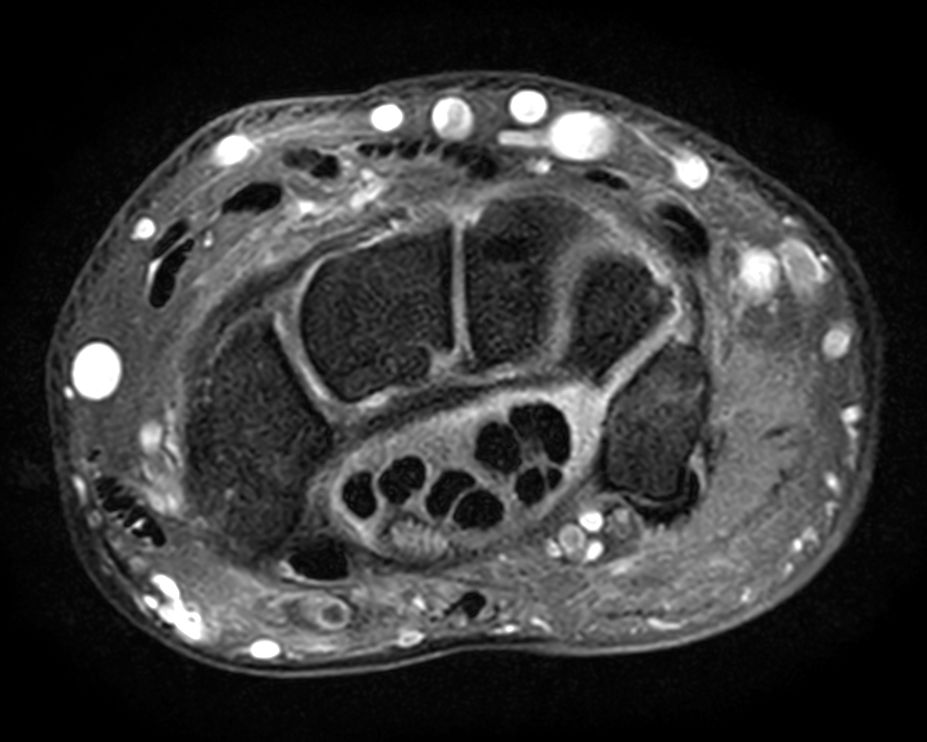

Off-center imaging of the Wrist with the dS HandWrist 16ch coil. Compressed SENSE is used to speed up the entire exam with virtually equal image quality.2.